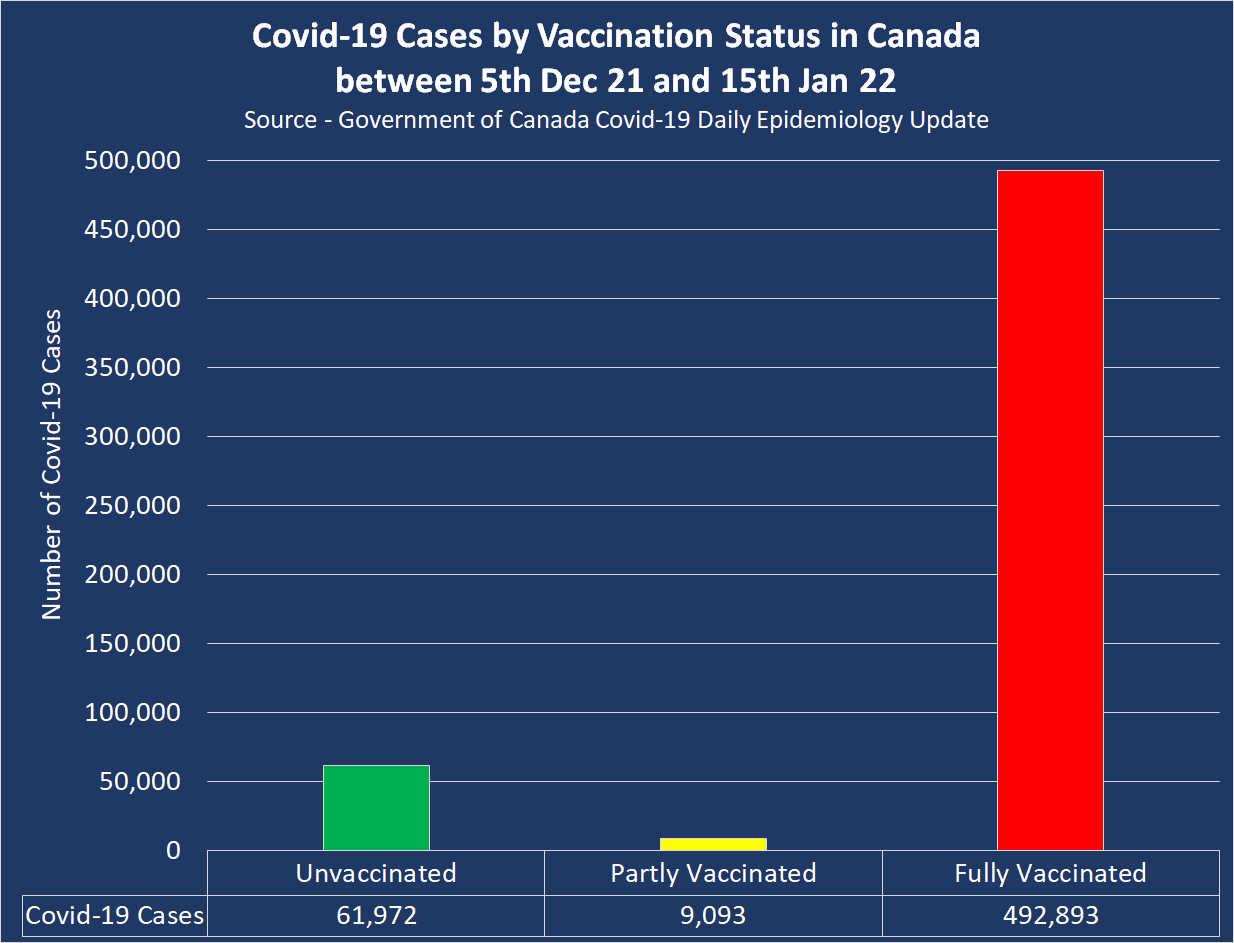

https://dailyexpose.uk/2022/02/06/canada-gov-data-suggests-fully-vaccinated-developing-ade/

Read article